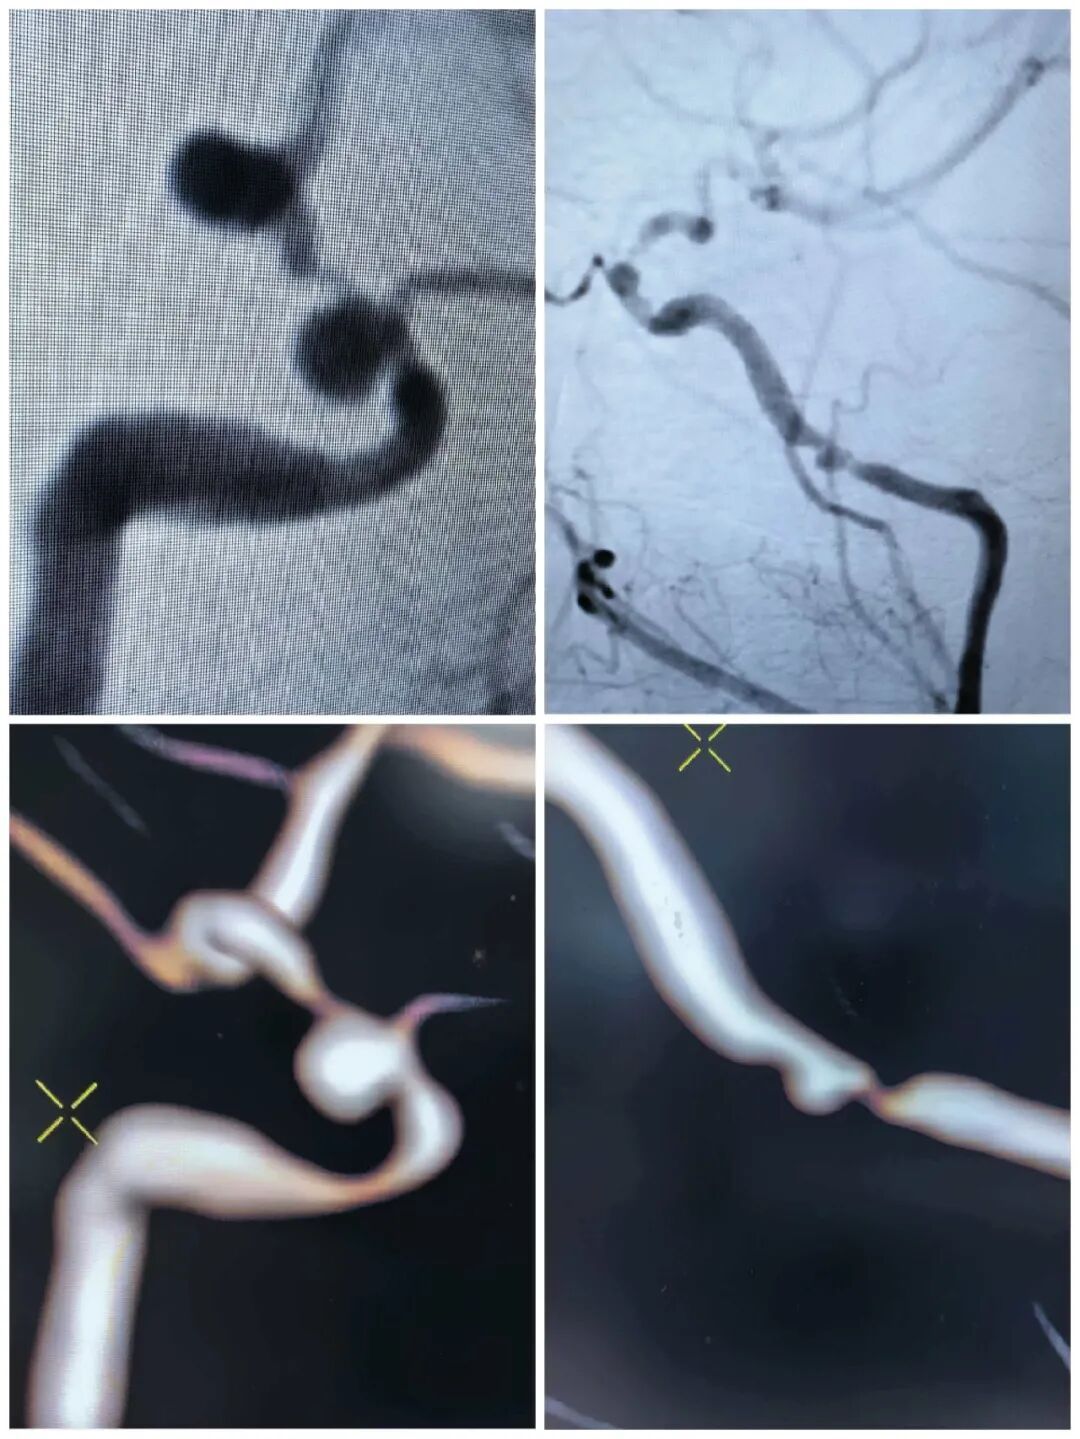

前不久,刘女士因“头痛头晕”来到瑞金医院舟山分院吴瀚博医生门诊就诊。进一步检查后,医生发现,她的问题远比想象中复杂:不仅存在脑动脉瘤,动脉瘤近端和远端血管还合并串联性重度狭窄。

更棘手的是,刘女士数年前曾因颅内肿瘤接受过放射治疗。放疗虽然杀死了肿瘤,却也悄然摧毁了血管的健康——血管壁纤维化、内膜增生,变得比常人更脆、更不规则。

面对这一险情,瑞金医院舟山分院迅速启动与总院的联动机制。瑞金医院神经外科江泓主任医师参与会诊,制定了一套“通路与拆弹同步”的终极方案:先以球囊精准扩张狭窄段,打通生命通道,再立即置入血流导向装置,让动脉瘤彻底隔绝。

手术由江泓主任医师主刀,张欧医生及吴瀚博医生担任助手。术中,团队凭借精湛技术,成功对两处串联性重度狭窄实施精准球囊扩张,并在高难度血管条件下,顺利置入一枚血流导向装置及一枚辅助支架。

术后即刻造影显示,刘女士远端血管血流恢复通畅,提示缺血风险得到有效解除;同时,动脉瘤内可见明显造影剂滞留,提示动脉瘤已被成功隔绝,出血风险明显下降。手术获得圆满成功。